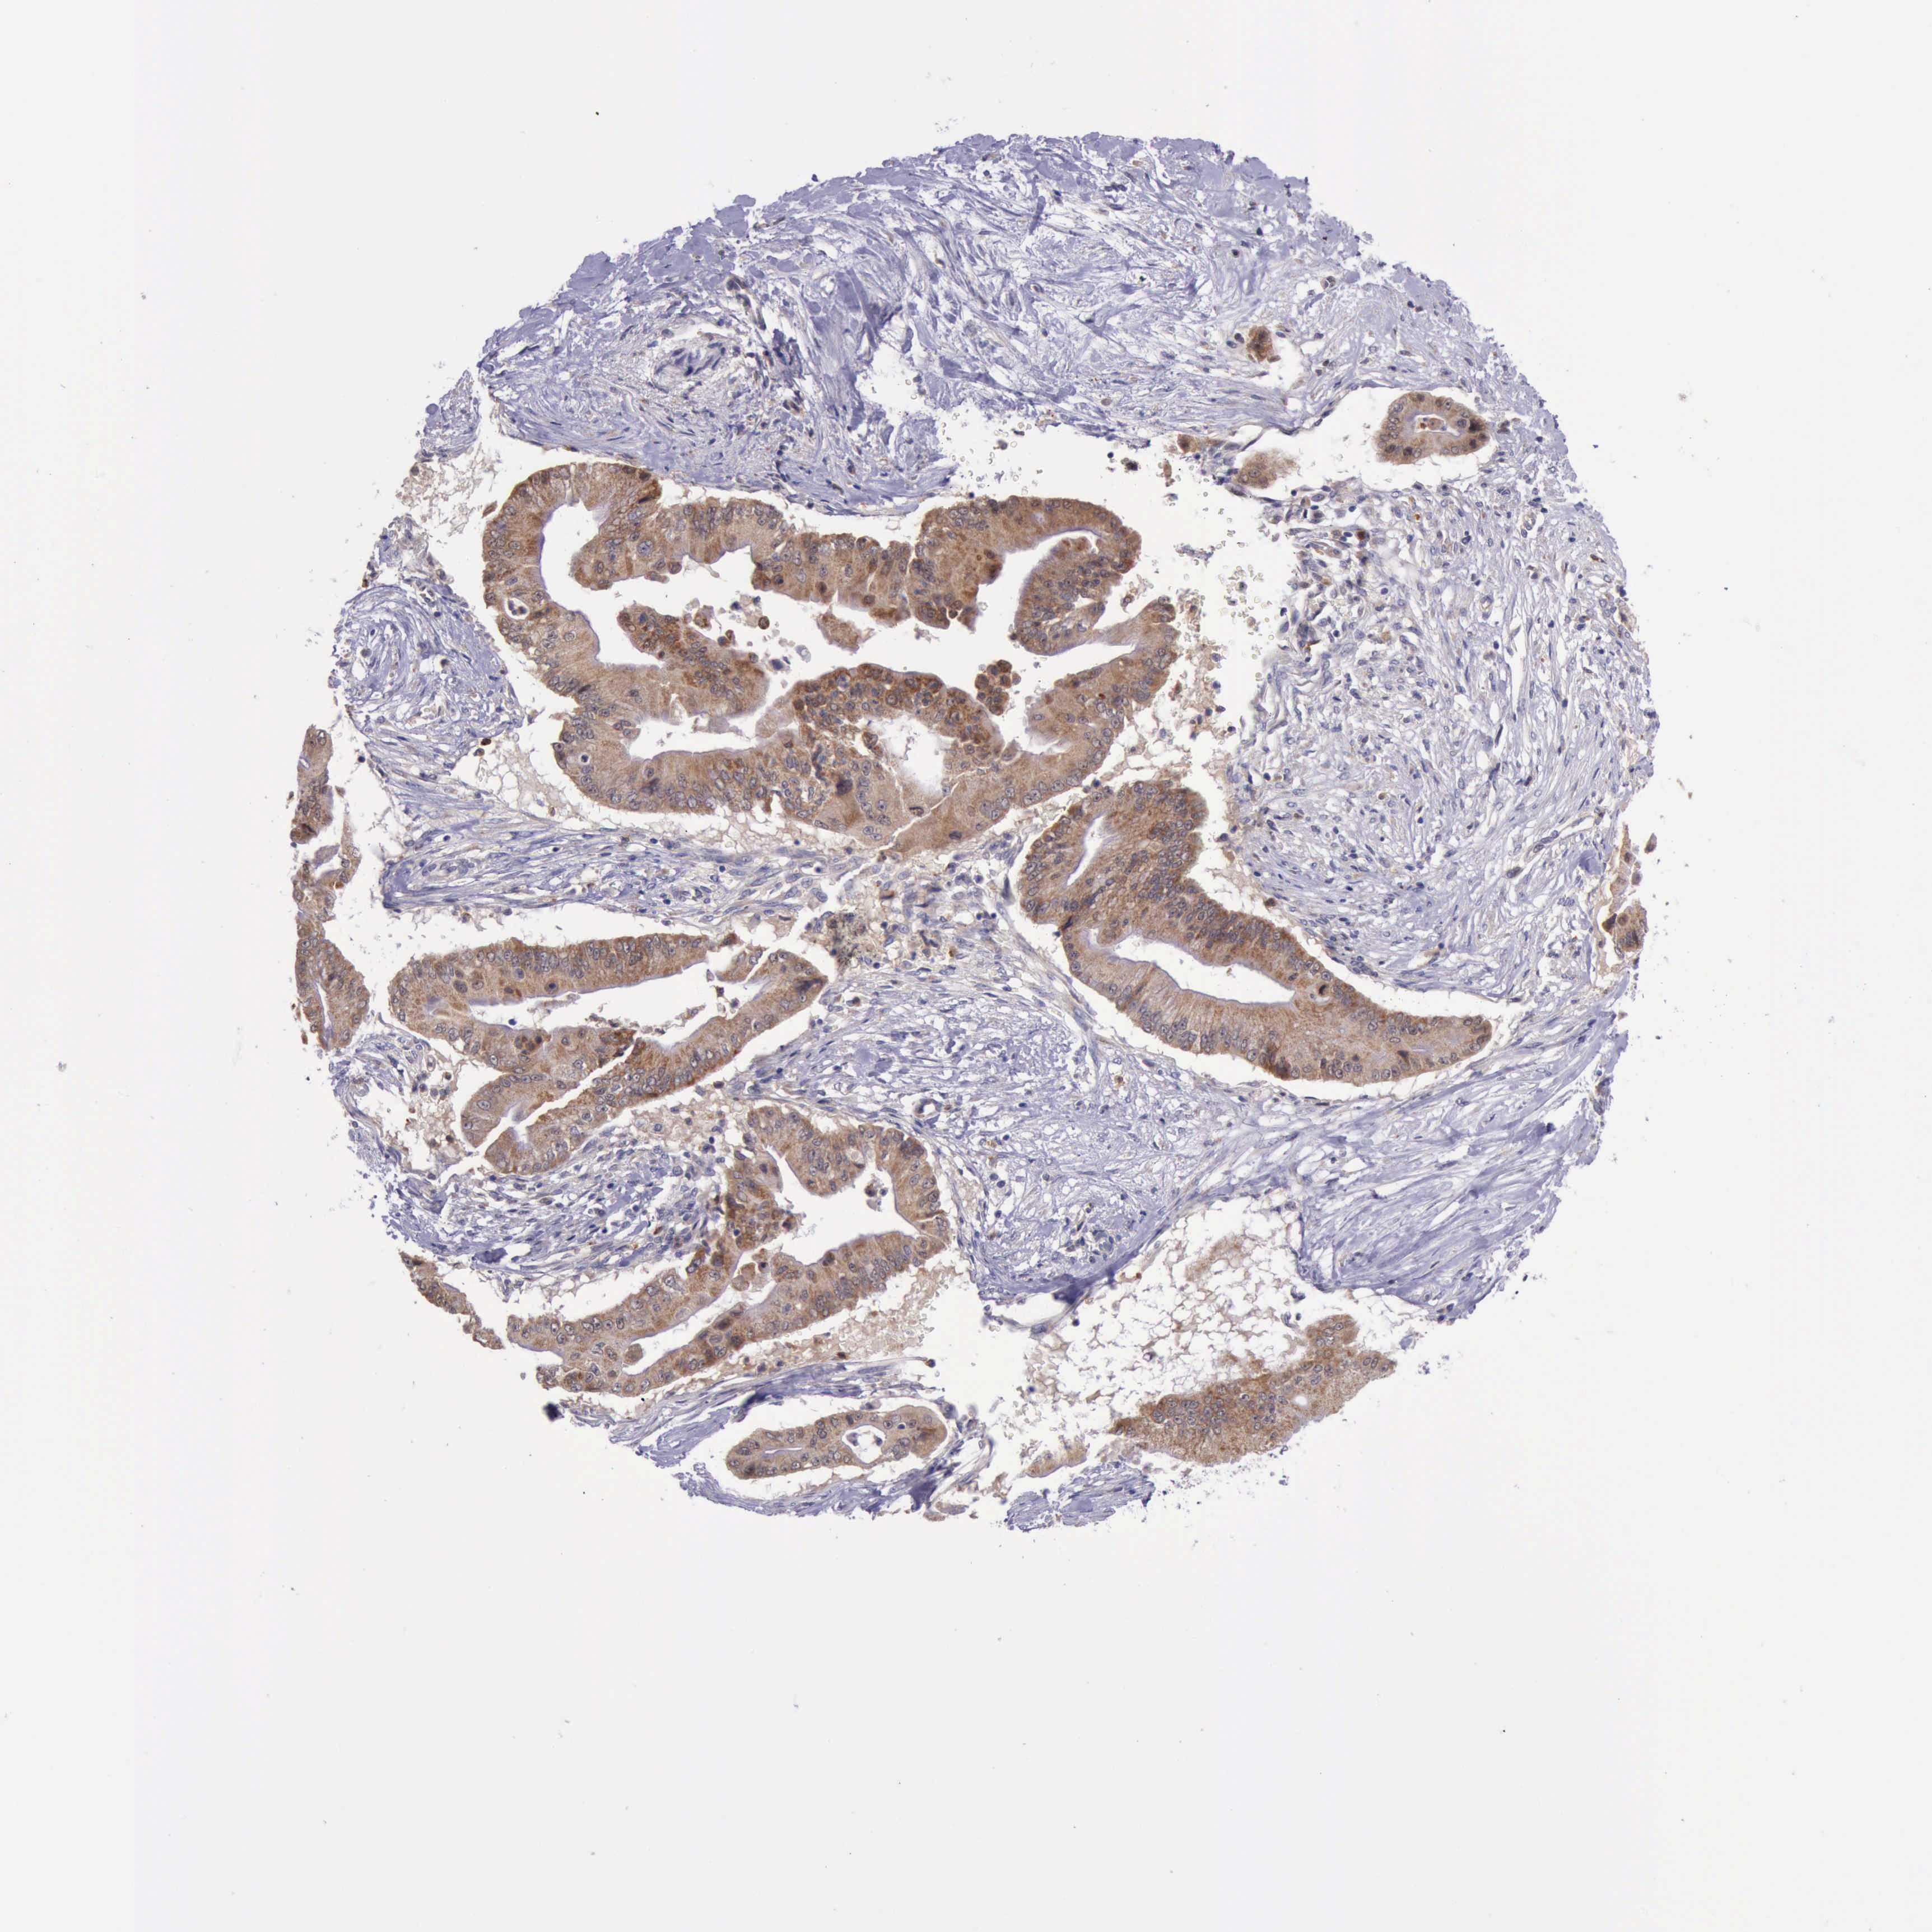

PANCREATIC CANCER - Protein expressioni

A mouse-over function shows sample information and annotation data. Click on an image to view it in a full screen mode. Samples can be filtered based on level of antibody staining by selecting one or several of the following categories: high, medium, low and not detected. The assay and annotation is described here.

Note that samples used for immunohistochemistry by the Human Protein Atlas do not correspond to samples in the TCGA dataset.

Antibody stainingi

Antibody staining in the annotated cell types in the current human tissue is reported as not detected, low, medium, or high, based on conventional immunohistochemistry profiling in selected tissues. This score is based on the combination of the staining intensity and fraction of stained cells.

Each image is clickable and will lead to virtual microscopy that enables deeper exploration of all samples and also displays staining intensity scores, fraction scores and subcellular localization as well as patient and tissue information for each sample.

Antibody HPA001208

Staining

High

Medium

Low

Not detected

Intensity

Strong

Moderate

Weak

Negative

Quantity

>75%

75%-25%

<25%

None

Location

Nuclear

Cytoplasmic/membranous

Cytoplasmic/membranous,nuclear

Adenocarcinoma, NOS